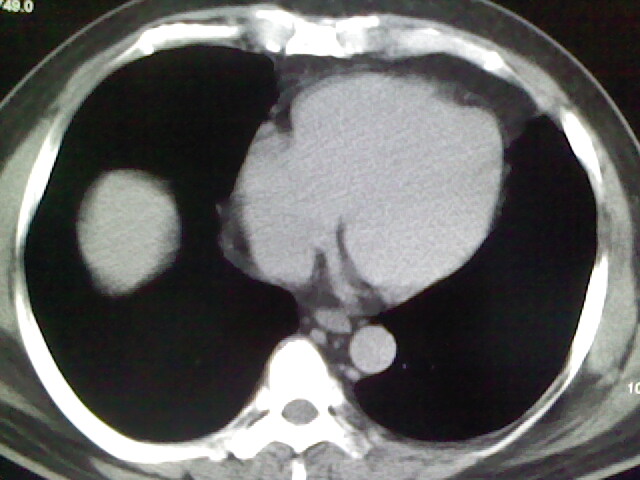

标题: CT17932:临床怀疑肺栓塞

男,34岁,自觉右侧胸痹,胸闷3天余

两肺纹理增多,余未见明确异常。

未见明显异常。图像上看此患者比较肥胖,建议查下心超

肺纹理分布较均匀,暂不提示肺梗塞